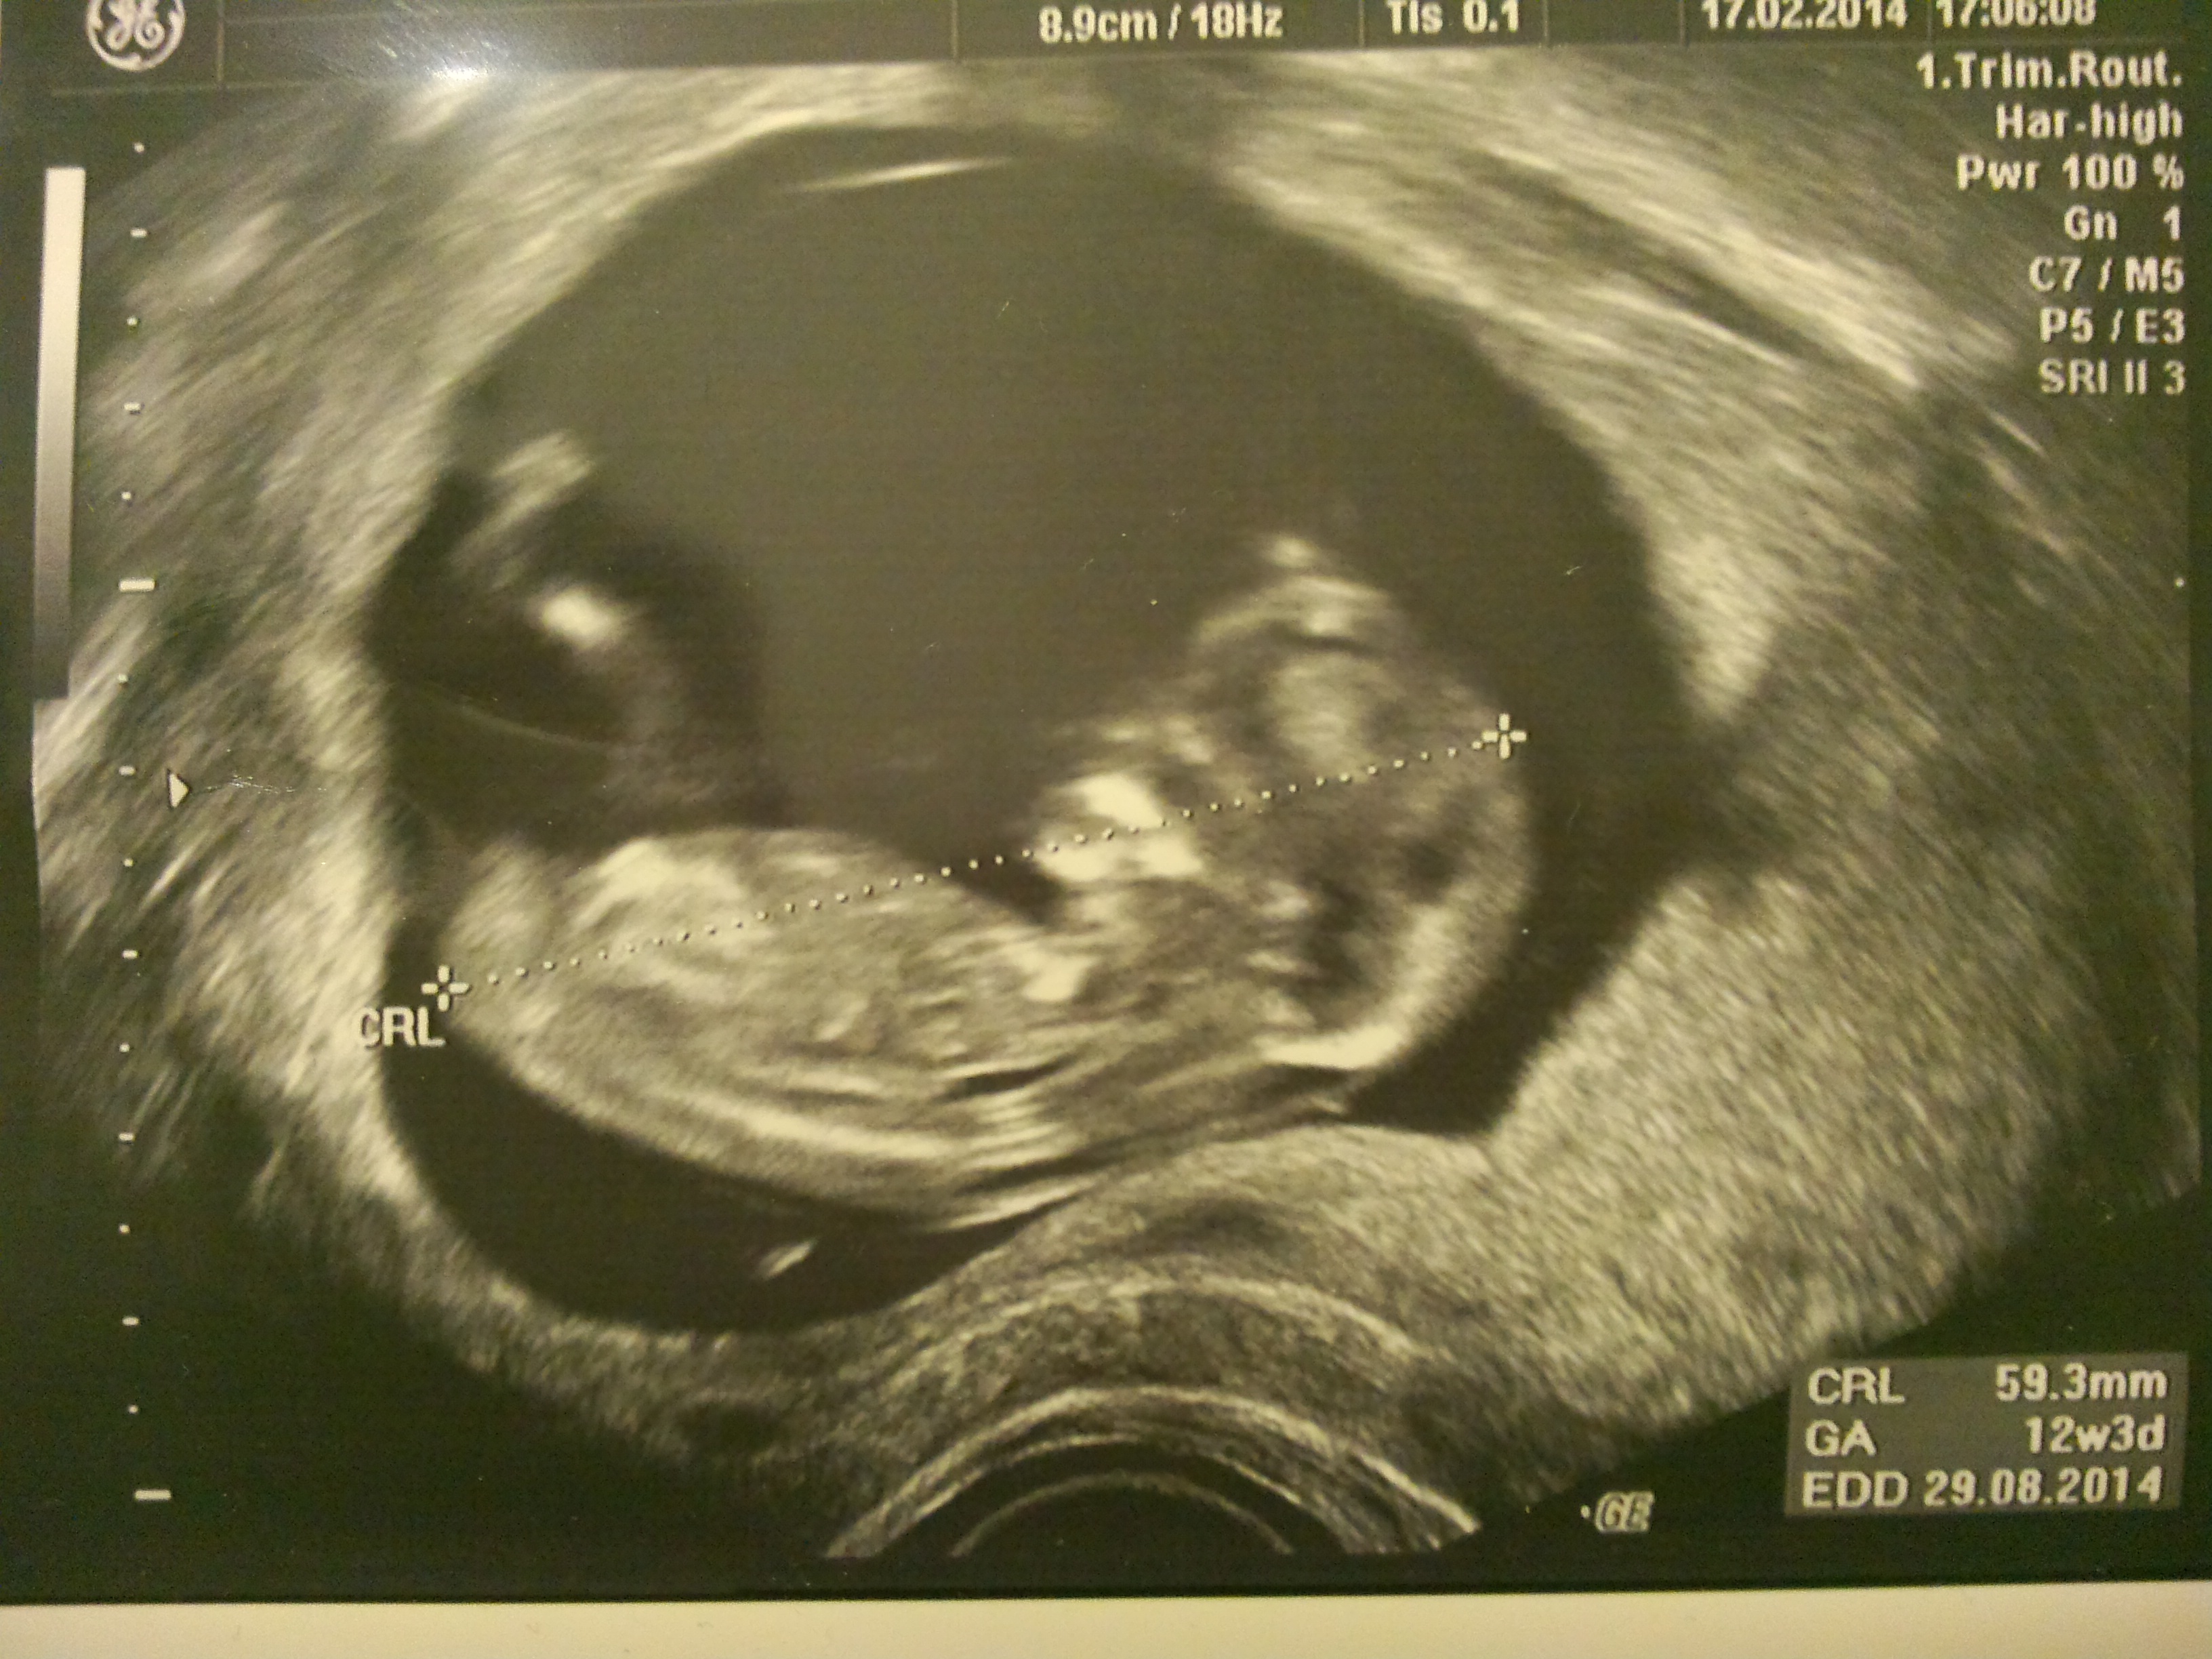

I can't discern any nub here but then I'm a beginner at this (first child!). It looks to be the nub might be obscured or hidden by baby's legs? Does anyone see anything I'm missing?

To me, it looks like baby's hips are rolled slightly toward the screen and the hip is obscuring the nub. My sons sono was like that...so fingers crossed for a boy! Lol.

hotdogz&boyz: Good point, I didn't notice that before but now I can see it. So this would mean that the visible leg in the picture is baby's right leg? All this time I was assuming it was the left leg (this is how inexperienced I am at this, haha) which would mean the groin area would be completely blocked. But if that's baby's right leg and the hips are slightly turned toward the screen then you can kind of see a partial nub or little protuberance of some kind between the legs. I hope that's a good sign but then again I understand that male and female nubs/protuberances tend to look a bit alike this early in the game, no?